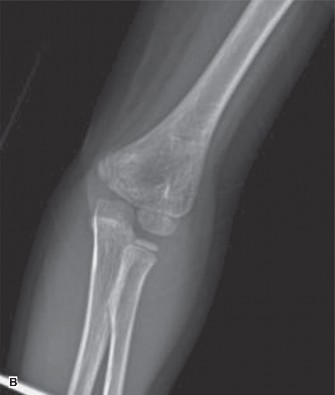

After seeing the above patient in follow-up in your clinic, you move to the next room and meet a 7-yearold who had a fall about 5 days ago. She has pain in the elbow when her splint is removed, and there is tenderness over the radial head and swelling of the soft tissues. Her distal motor, sensory, and vascular examinations are normal. You order new x-rays of the elbow and see the following (Fig. 10–7A and B).

Figure 10–7 A

Figure 10–7 B

The correct answer is (B). Obtaining x-rays of the ipsilateral forearm would be the next step for evaluation of this child. She has an obvious radial head dislocation. Isolated radial head dislocations are thought to not happen in children—they are usually associated with an injury to the ulna which can be a very subtle ulnar bow. Failure to recognize the ulna deformity can compromise the success of any attempt at radiocapitellar joint reduction—the ulna often has to be corrected via an osteotomy to allow for the radiocapitellar joint reduction. A full forearm x-ray on this patient confirmed that there was a subtle ulnar bow relative to a straight line drawn down the x-ray (Fig. 10–8).